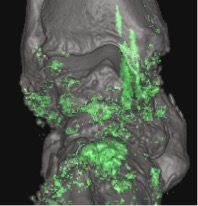

DUAL-ENERGY CT (DECT)

DECT demonstrates diffuse urate deposits in gouty arthritis (green areas)

Corresponding CT shows diffuse chondrocalcinosis

Generation of dual-energy CT image

CT technique that uses two separate x-ray photon energy spectra, allowing differentiation of tissues based on their attenuation properties at different energies.

Indications

Crystal arthropathies (gout, CPPD) – diagnosis confirmation/exclusion in subclinical disease, atypical presentations or gout-mimickers, problem-solving, monitoring treatment response by measuring disease burden.